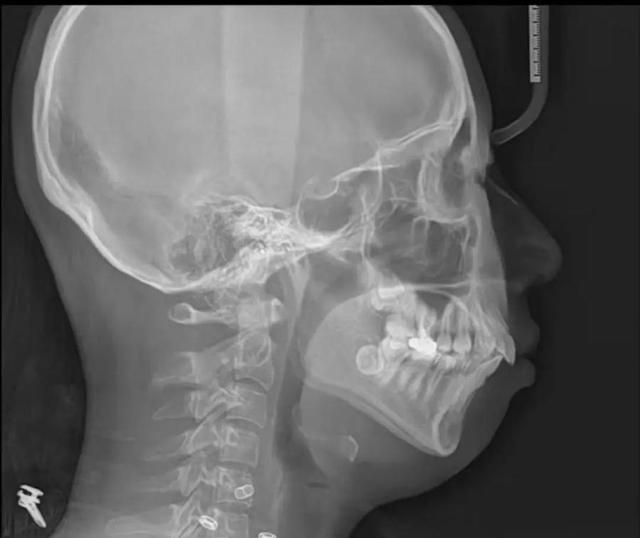

通过拍摄侧位片然后进行头影测量分析,可以更准确地评估下颌与颅骨的关系,确定下颌后缩的程度。